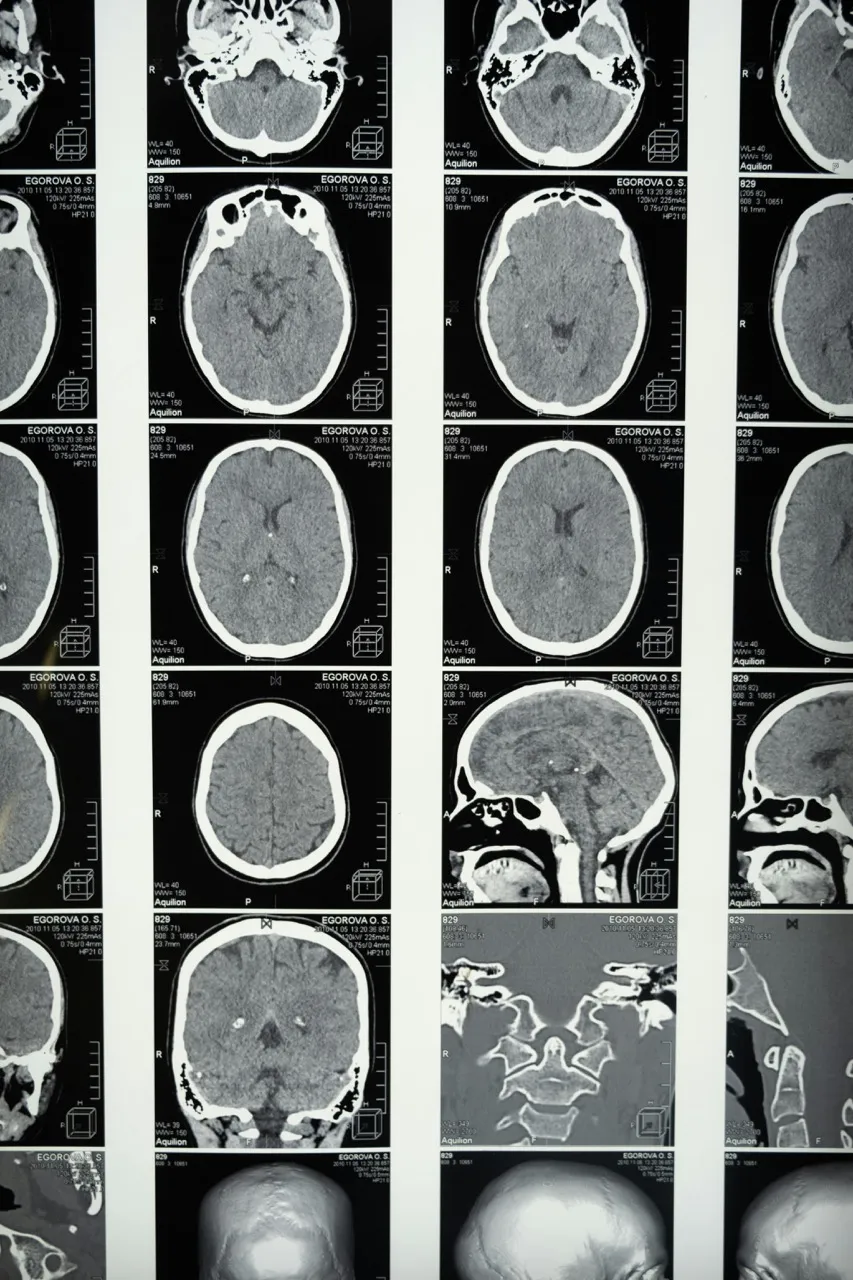

The idea that the brain drastically changes isn’t unfounded. According to Mariam Arain et al., the frontal lobe—the part of the brain responsible for a wide range of essential functions, including movement, cognition, and emotional regulation—doesn’t fully mature until around the age of 25. This late maturation is due to the brain’s “back-to-front” pattern of development, which means the prefrontal cortex is one of the last regions to fully develop.

What does that mean? Simply put, as the frontal lobe finishes developing, your brain’s “executive skills,” like judgment and decision-making, problem-solving, reasoning, impulse control, and planning, become more solid. The result? Fewer purely “gut-feel” choices, and more decisions guided by logic and reflection. A departure from the emotional volatility that most people experience in their teens and early 20s.

Banner photos by Cotton Bro Studios via Pexels.